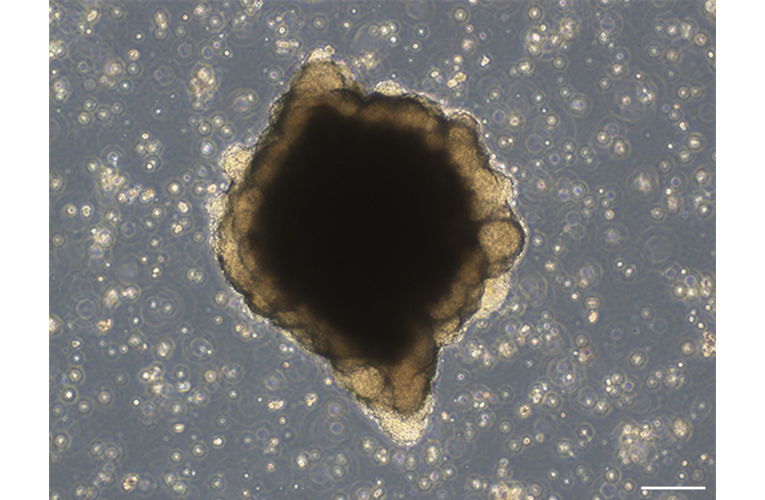

- Tool name: RCOL009 Colorectal cancer organoid

- Tool sub-type: Organoids

- Description: A series of novel patient-derived organoids (PDOs) have been constructed from different tumor tissue types under the Fukushima Translational Research Project, designated as F-PDO. F-PDOs form large cell clusters with a morphology similar to the original tumor and can be cultured for more than six months. Our comparative histological and comprehensive gene expression analyses have shown that the characteristics of F-PDOs were similar to their source tumors, even after long-term growth in culture conditions